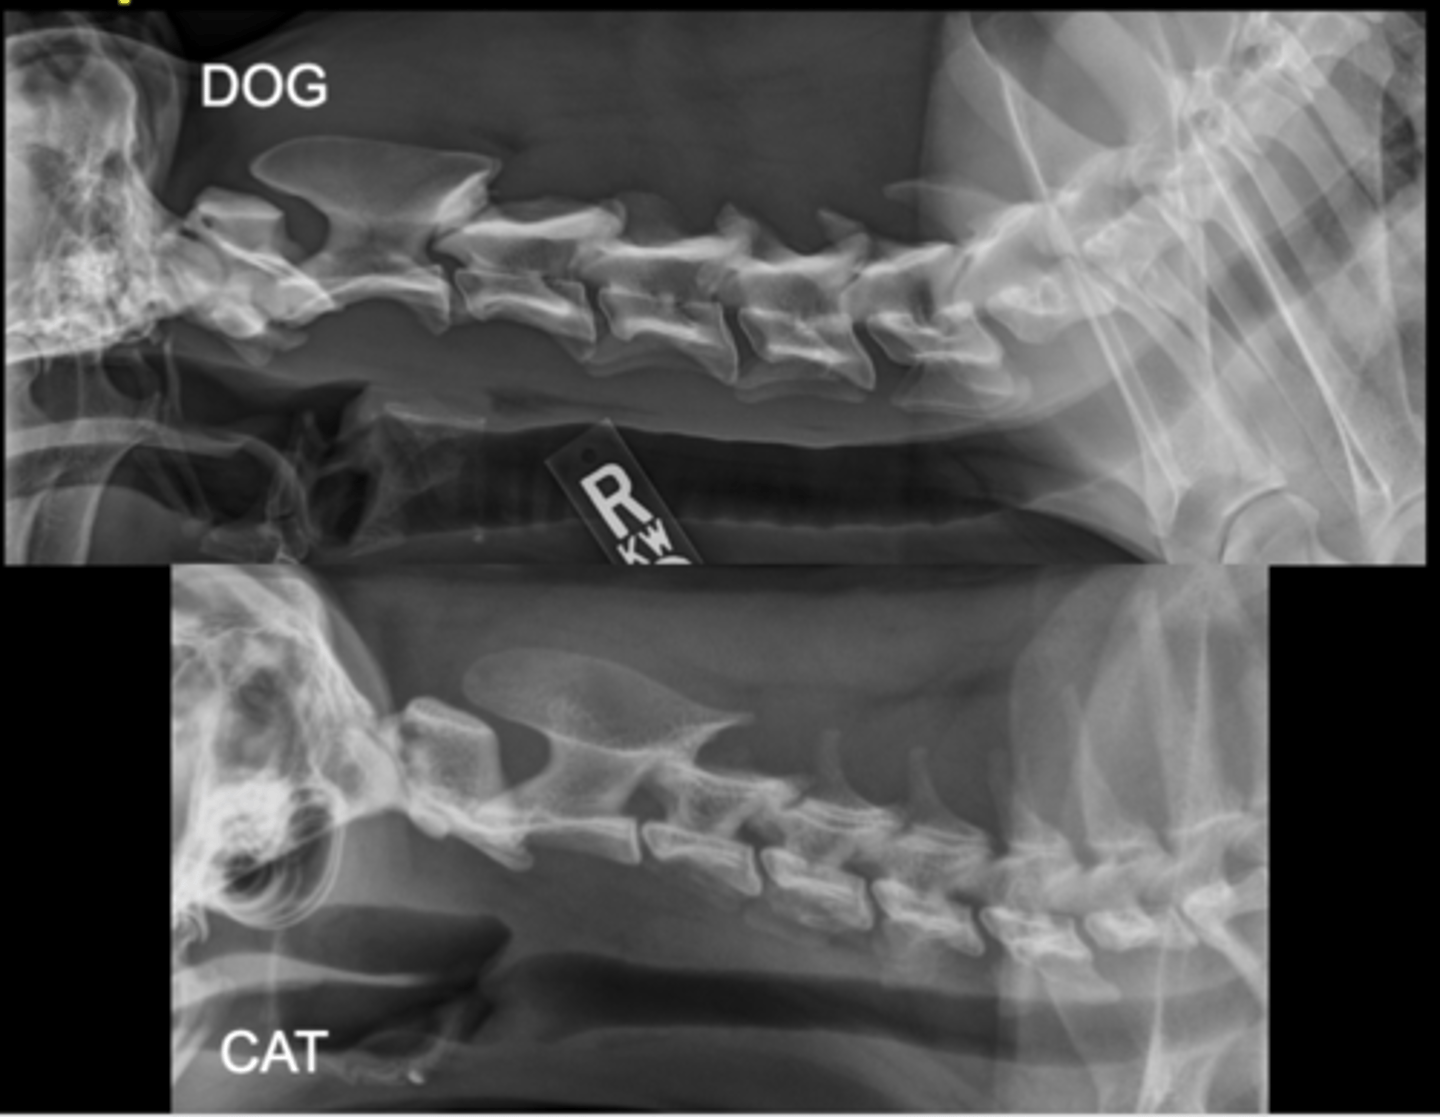

Equine Spine Lateral

Llama Spine Lateral

Bovine Spine Lateral

LG Animal Spine - Lateral image

• Patient usually standing

• Marker to indicate laterality of patient

LG Animal Spine - DV/VD image

• Only in smaller patients due to size

• Patient standing or under GA in sternal or dorsal recumbency